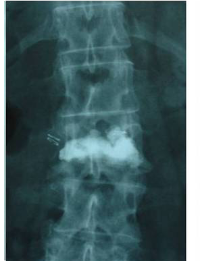

Caso clínico de una resección (corpectomía) y reconstrucción vertebral lumbar en una fractura estallido de nivel L4.